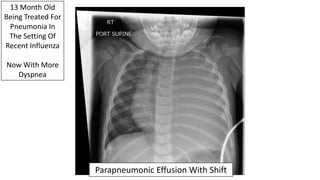

13 Month Old

Being Treated For

Pneumonia In

The Setting Of

Recent Influenza

Now With More

Dyspnea

Parapneumonic Effusion With Shift